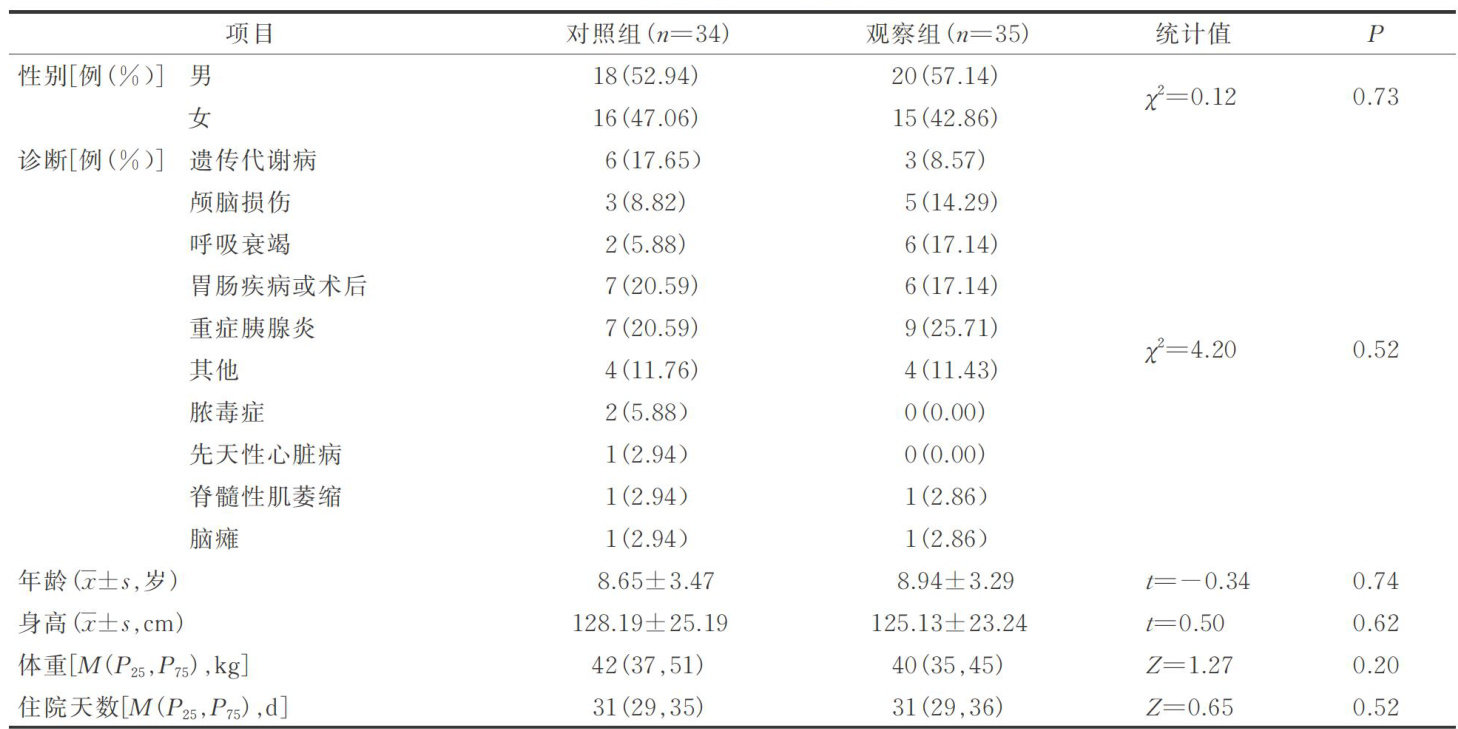

综合研究 | 前额发际至肚脐两点位置体表测量法在儿科监护室鼻肠管床旁盲插中的应用

综合研究 | 前额发际至肚脐两点位置体表测量法在儿科监护室鼻肠管床旁盲插中的应用